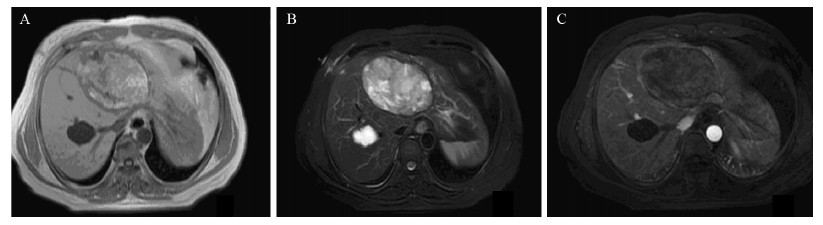

1 病例资料患者,女,45岁。因查体发现肝囊性占位1周,于2013年3月18日入住我院介入治疗科。门诊CT检查提示:肝内可见2个边界清晰、无明显强化低密度灶。较小的囊肿由于位于肝右叶且形态较小,未给予同步穿刺。较大的一个位于肝左叶,约10.6 cm×7.0 cm,压迫门静脉左支及左肝管,远端肝内胆管扩张,见图 1。入院时查体:肝左叶剑突下4 cm,质软、无压痛,余无异常。实验室检查:血清C反应蛋白5.58 mg/L、白细胞5.66 ×109/L、CA19-9 7.51 u/ml (参考值0~39 u/ml)、CA24-2 6.3 u/ml (参考值0~12 u/ml)、AFP 4.7 μg/L (参考值0~20 μg/L),入院诊断:肝囊肿;拟给予肝囊肿穿刺引流联合无水乙醇硬化微创治疗。

| A:plain CT scans showed two low-density lesions in both hepatic lobes,the left lobe's cyst was bigger and measured as 10.6 cm ×7.0 cm in diameter,with a clear demarcation;B:the contrast enhanced CT scan showed that there were uniform low-density areas inside the cyst and the cyst wall was without significant enhancement;C:the boundaries between the cyst wall and the surrounding structures was unclear,the left portal vein and left hepatic duct were pressed and the distal of intrahepatic bile duct was dilated 图 1 肝囊肿穿刺引流前CT平扫及增强表现 Figure 1 CT findings of plain scans and contrast enhanced scans before a percutaneous transhepatic drainage of hepatic cyst |